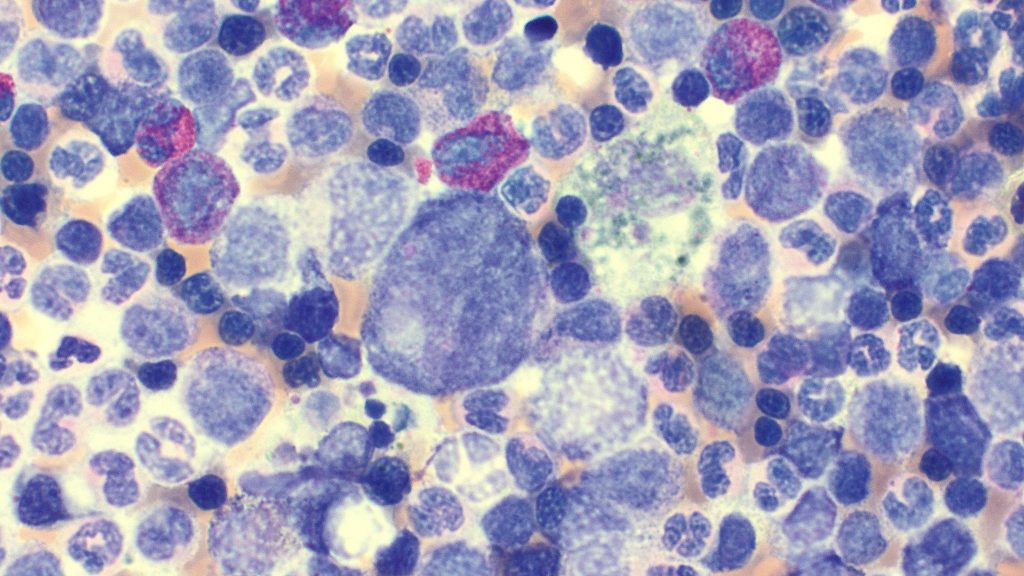

Hemophagocytosis

Click me